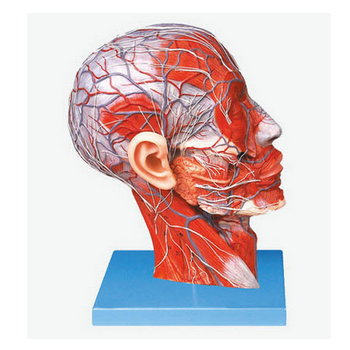

頭部正中矢狀切面附血管神經(jīng)模型 GD/A18210功能介紹■ 該模型顯示頭頸部正中矢狀切面內(nèi)、外側面的局部形態(tài)及其血管和神經(jīng)等結構,共有100個部位指示標志。■ 尺寸:自然大,高27cm,寬20cm,...